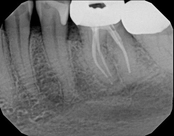

Non-surgical root canal treatment:

Before

After

6-month follow-upThe patient presented with mild pain, a cavity, and a broken filling was evident. After performing diagnostic testing, the diagnosis was: irreversible pulpitis, symptomatic periradicular periodontitis. Root canal therapy was done and the tooth healed well and is still functioning.